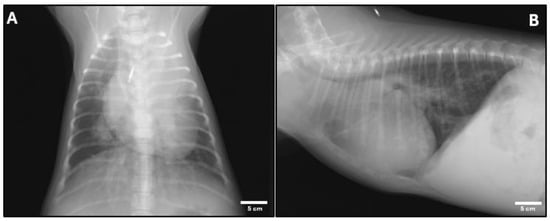

2. Case Presentation